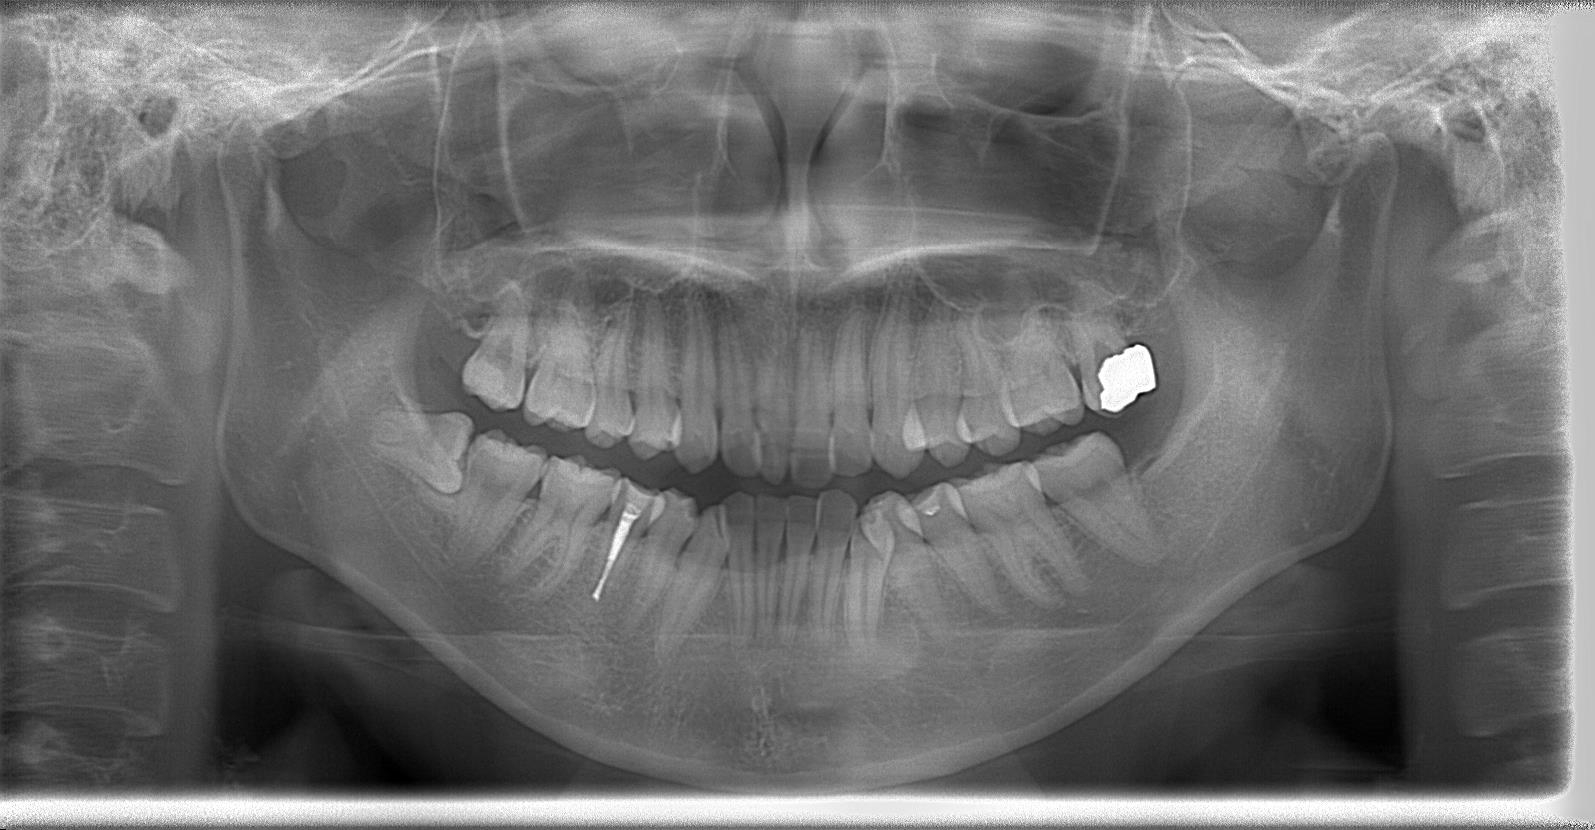

レントゲン写真の状態を御覧ください。

術前パノラマレントゲン写真

部位:右上8番骨性完全埋伏歯

部位:右下8番骨性完全埋伏歯

部位:左上8番骨性完全埋伏歯

部位:左下8番骨性完全埋伏歯